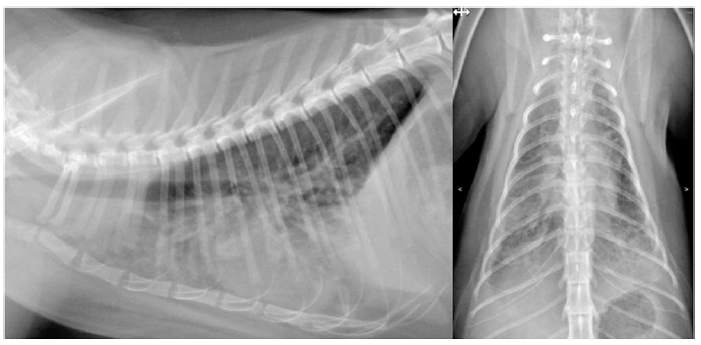

第18天,由于担心微丝蚴死亡导致呼吸急促,额外开具了泼尼松龙(2 mg/kg),但药物未被主人领取。当晚因急性呼吸窘迫发作而被送往急诊科,呼吸频率92次/分,氧饱和度83%,X光显示弥漫性肺间质纹理(图4)。猫被收治入院,接受氧疗(15 L/min)、地塞米松(0.1 mg/kg,静脉注射,q12h)以及氨苄西林-舒巴坦(30 mg/kg,静脉注射,q8h)。

图4. 在接受莫西克汀和多西环素治疗后出现的X光间质性肺纹理。左为右侧位图,右为背腹位图。